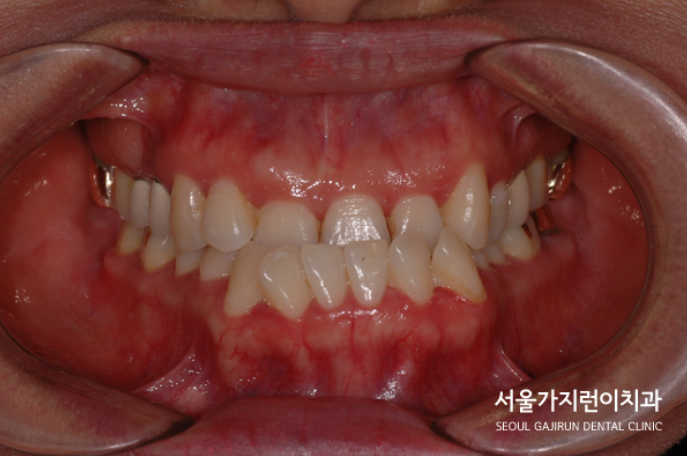

환자분의 경우 주걱턱교정이 시급한 경우였는데요. 주걱턱으로 인해 퉁명스러워 보이는 이미지를 갖고 있어서 외모적으로도 상당한 고민을 갖고 있었던 사례였습니다. 특히 하악골이 왼쪽으로 치우쳐진 비대칭도 있었기 때문에 교합 상태가 좋지 않았는데요.

주걱턱도 개선해야 했지만 정상교합으로 돌려놓기가 쉽지 않았는데요. 환자분의 경우 치료 1년 후 안정적으로 교정치료를 마쳤으며 6년이 지난 지금까지 안정적인 상태를 유지하고 있었습니다. 이 사진을 보면 교정이 잘 이루어져 재발하지 않았다는 것을 확인할 수 있는데요.